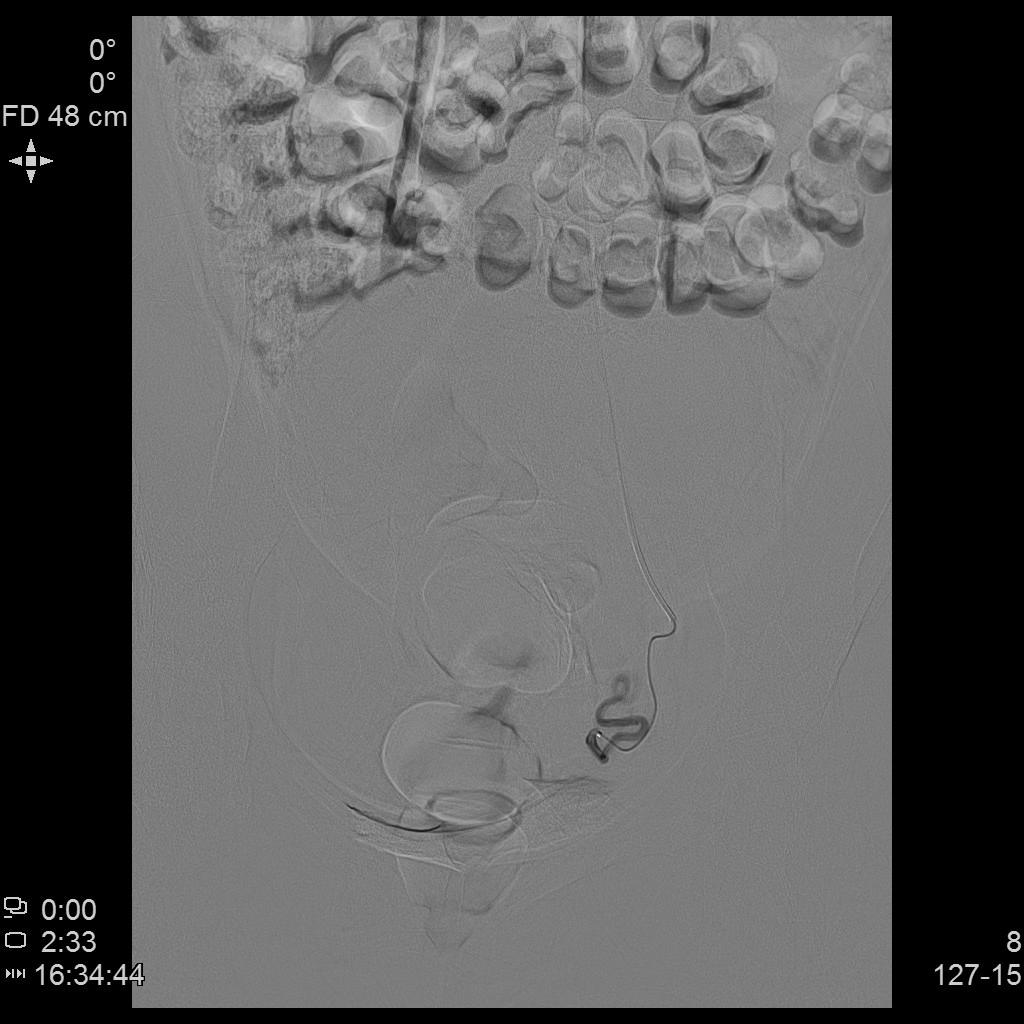

- 经桡动脉入路插管,微导管进一步超选插管右侧子宫动脉主干造影确认位置,随后行动脉栓塞治疗。

- 微导管进一步超选插管左侧子宫动脉主干造影确认位置,随后行动脉栓塞治疗。